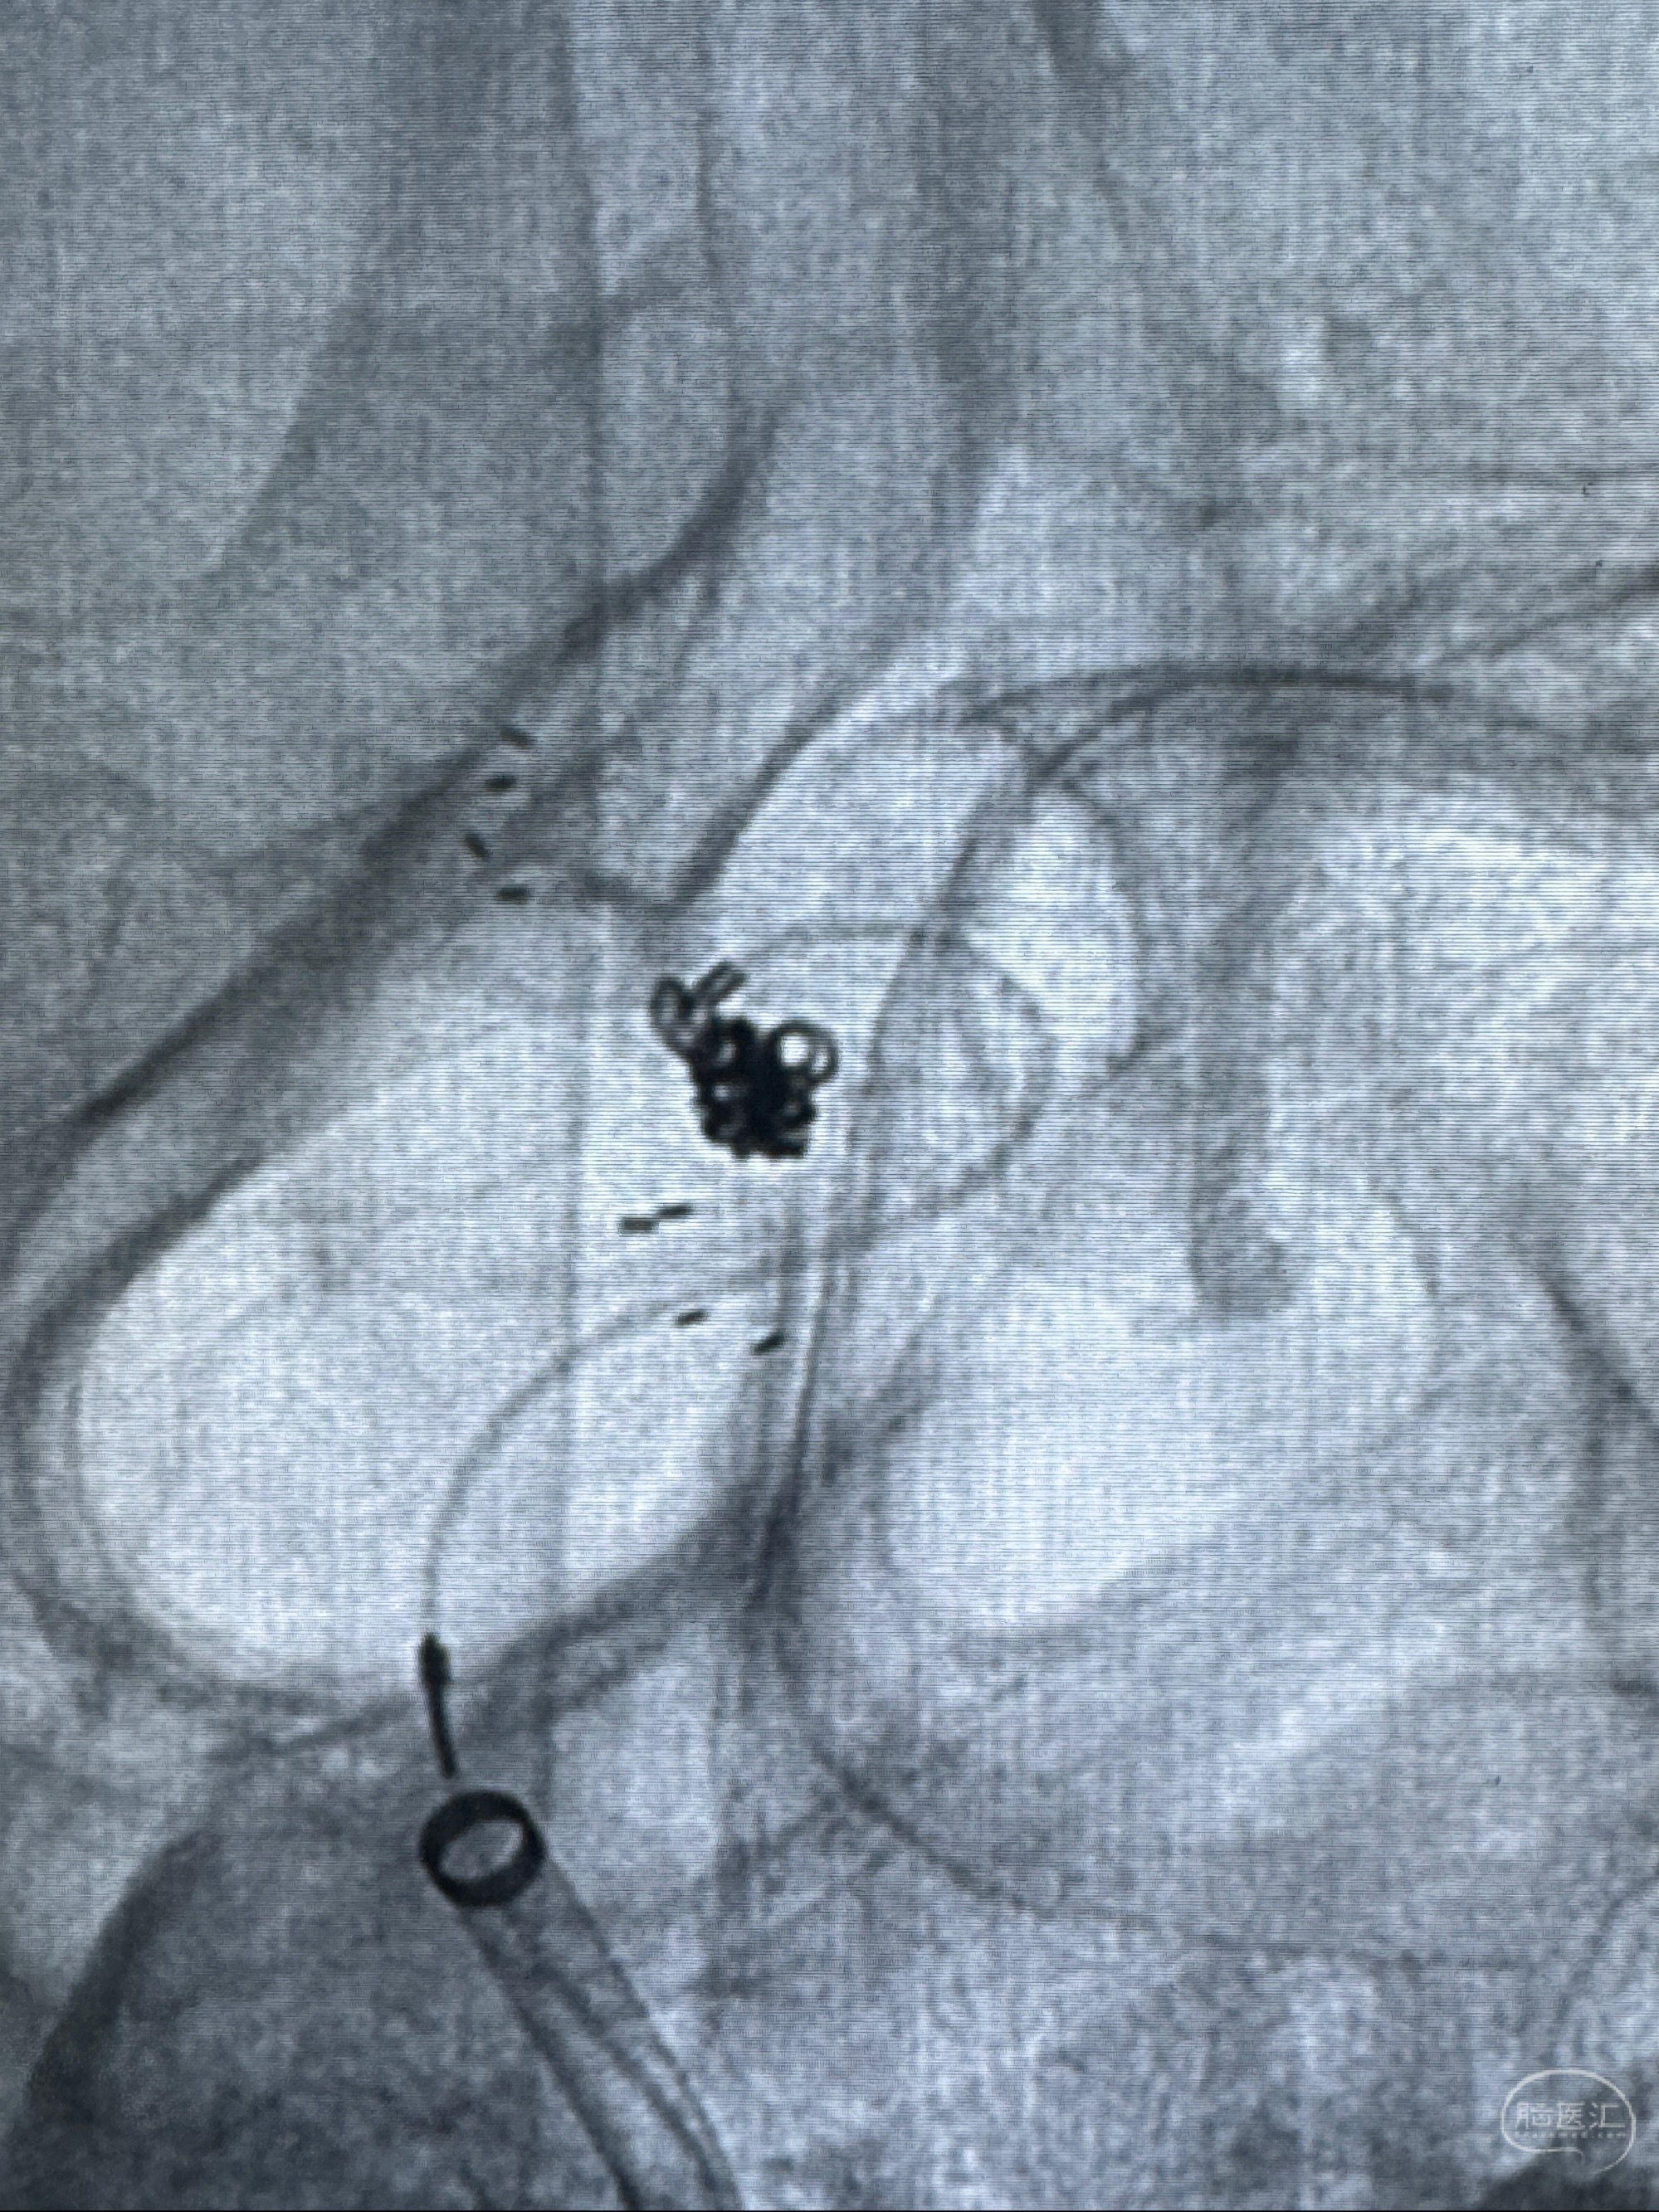

2023-11-13DSA:左侧颈内动脉眼动脉后壁动脉瘤

2023-11-29全麻下行NeuroformEZ4.5-20mm支架辅助栓塞